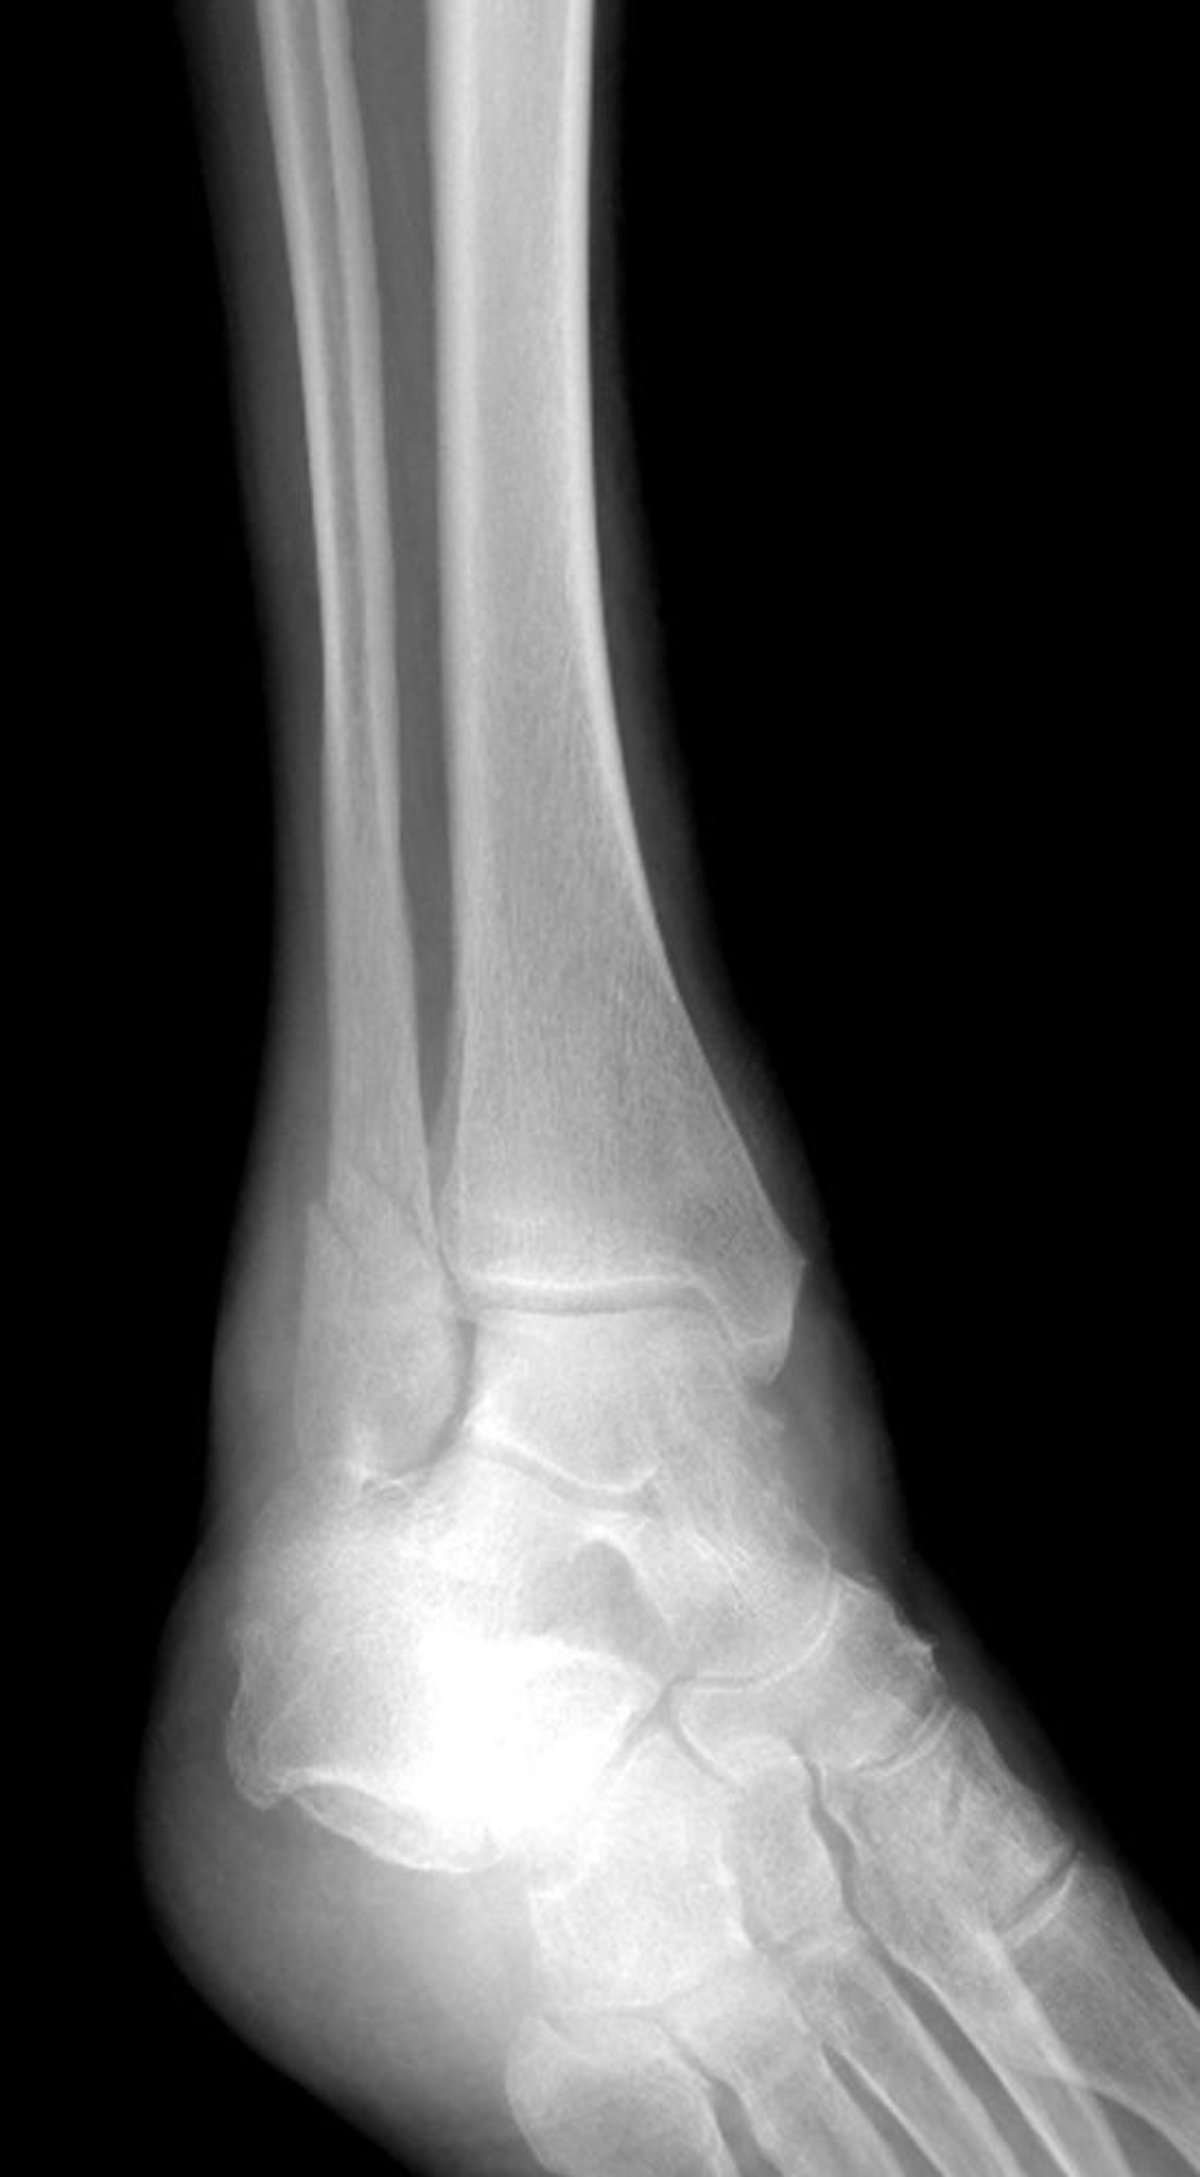

Перелом латеральной лодыжки

Это перелом латеральной лодыжки, но сочетанный с переломом медиальной лодыжки.